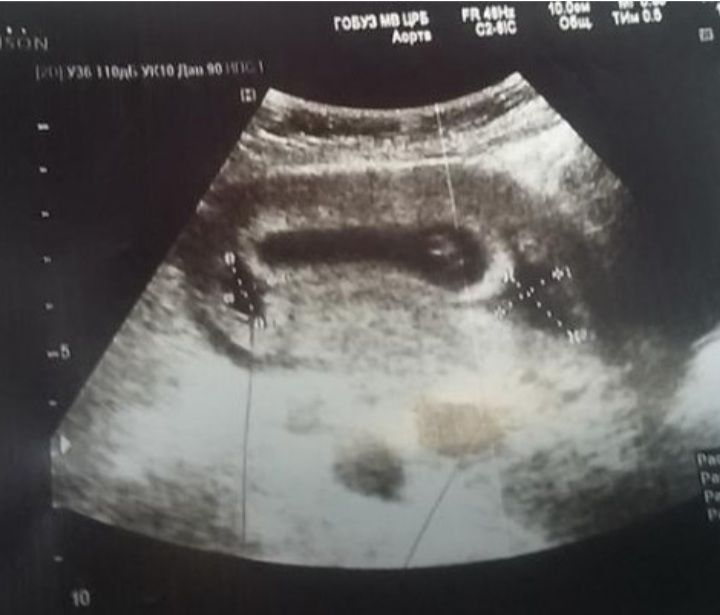

У меня в прошлую б на сроке 7-8 недель нашли две гематомы и деформированное пя,принимала магний,утрожестан,свечи с папаверином и аскорутин для укрепления сосудов.На первом скрининге уже всё было хорошо и никакой гематомы. Изображение